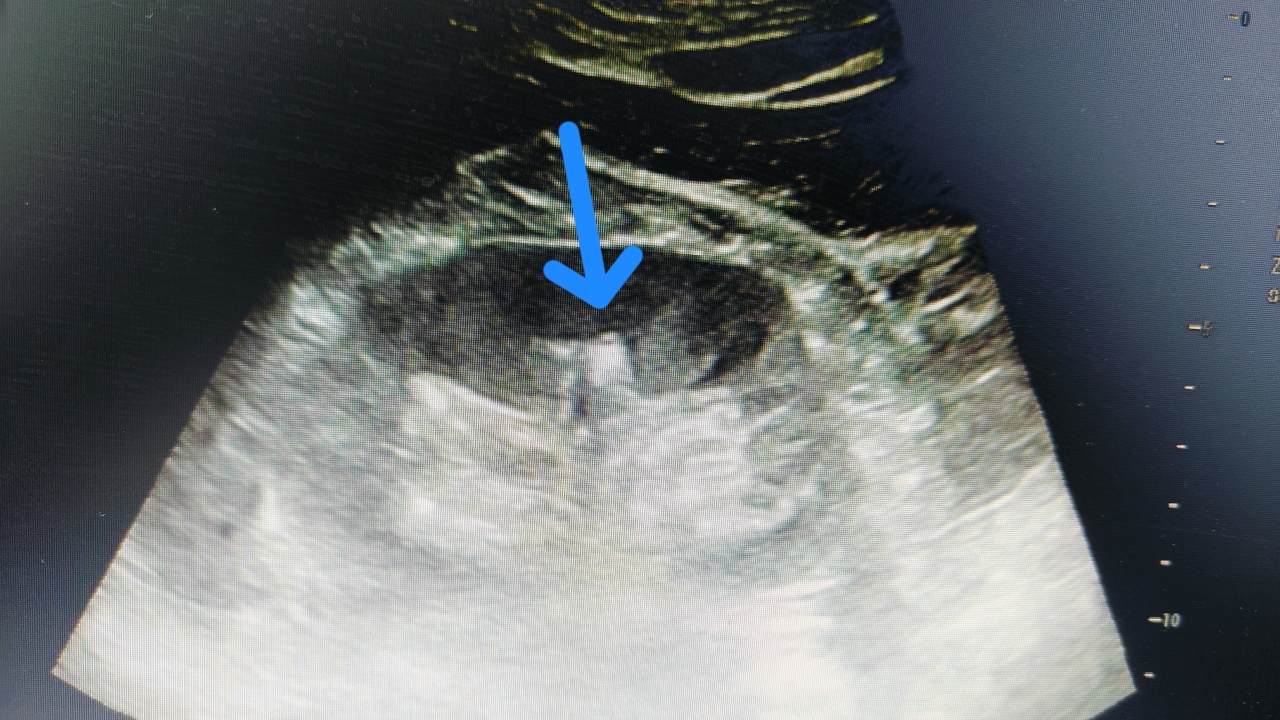

肾结石彩超就像给肾脏做一次“声波扫描”。医生拿着探头在你腰上滑来滑去,超声波就像“侦探的雷达”,遇到结石就会反射回来,在屏幕上形成亮闪闪的“小光团”——那就是结石“本石”啦!

结石在彩超下会“自带阴影”,就像妖怪现形时的黑雾,超好辨认!

如果结石堵住输尿管,彩超还能看到“肾积水”(肾脏被尿憋大了),就像水管堵了,水漫金山!